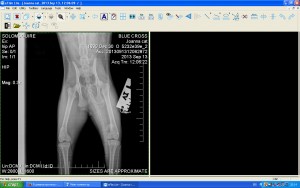

За съжаление новините от Йоана не са добри.Няколко месеца след осиновяването и се появи проблем с крачетата.Наложи се да се направи операция на пателата(разместени капачета на коленете),много рядка диагноза за котка,но "нашата" Йоана твърдо е решила да не е обикновенна котка.

Но дори и след операциите на крачетата,Йоана някакси има странна стойка.Не се отразява на подвижността и,не дава признаци да има болка или дискомфорт,но задните и крачета са някакси в неестествена позиция.

Заведохме я за снимка в Син кръст,казаха че операцията е направена добре и няма нужда от друга.